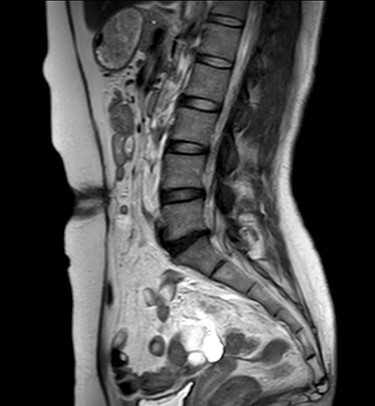

The patient did well after surgery. Follow-up MRI taken 10 days after surgery confirmed the absence of hernia and closure of the fascial defect (Figs 9 and 10).